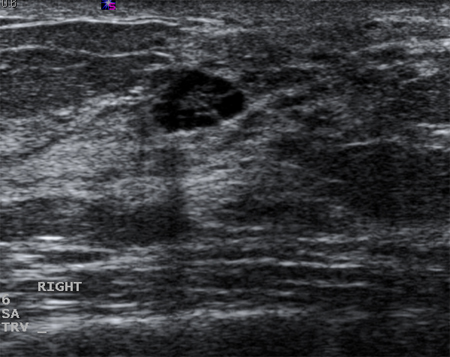

Imagem ultrassonográfica de um carcinoma complexo

Cortesia do Dr. Lane Roland, Universidade de Louisville; usado com permissão